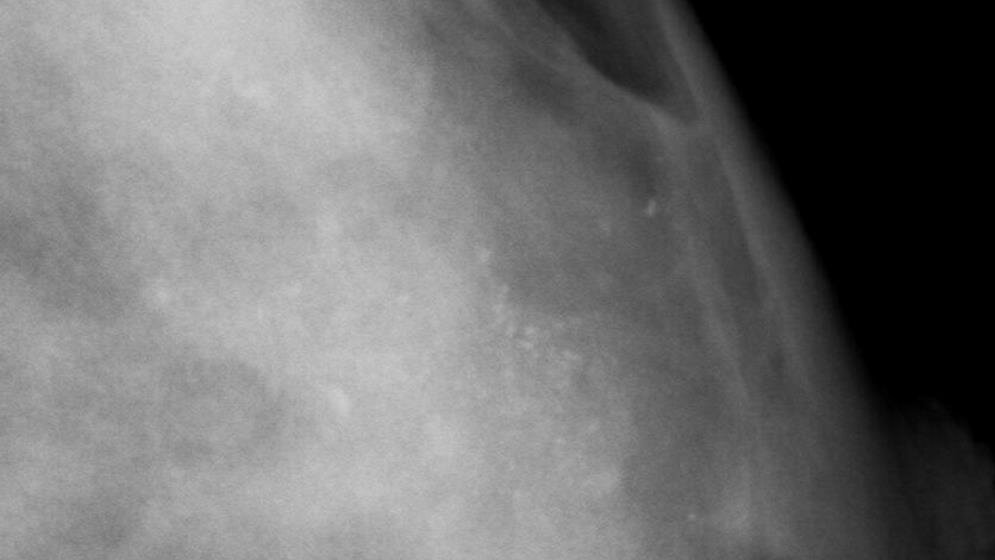

Seit 2009 wird die Brustkrebs-Früherkennungsuntersuchung (Mammographie-Screening) deutschlandweit angeboten. Dazu bekommen Frauen im Alter zwischen 50 und 69 alle zwei Jahre eine Einladung zur Mammographie und eine Informationsbroschüre (Merkblatt). Der Gemeinsame Bundesausschuss (G-BA) beauftragte das Institut für Qualität und Wirtschaftlichkeit im Gesundheitswesen (IQWiG), eine Entscheidungshilfe zu entwickeln, um Frauen beim persönlichen Abwägen von Vor- und Nachteilen besser zu unterstützen. Diese Entscheidungshilfe hat das IQWiG jetzt in ihrer finalen Fassung veröffentlicht. Darin eingeflossen sind Vorschläge aus der Anhörung ebenso wie Ergebnisse weiterer Nutzertests.

Der Auftrag wurde in zwei Stufen bearbeitet: Die erste Stufe umfasste die Überarbeitung des seit 2010 im Mammographie-Programm eingesetzten Merkblatts und des Einladungsschreibens. Dieses vom IQWiG erarbeitete Merkblatt wird bereits seit Januar 2016 mit den Einladungen zur Mammographie verschickt.